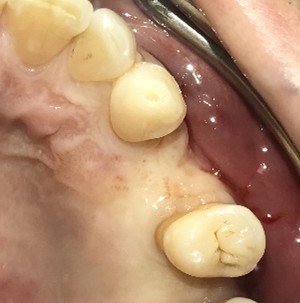

女性Sさん 60代(インプラント)

左下が腫れていて、噛むと痛い。

治療内容

左下ブリッジの支台になっている大臼歯が、歯根の破折を起こしていましたので、抜歯しました。奥歯3本欠損のところに、2本インプラントを埋入しました。

所感

奥歯3本歯のないところを補う方法は、インプラント、あるいは取り外しの部分入れ歯、という2つの方法があります。部分入れ歯は支台になっている歯に負担がかかるため、問題が起きた時には、支台になっている歯がダメになり、更に抜歯になる可能性が大きいです。最初は3本の欠損から、4本、5本と歯がないところが拡大してしまいます。また、義歯は異物感が大きく慣れるのが大変で、上下自分の歯どうしで噛む感覚と同じようには噛むことができません。

インプラントは、単独で植立し他の歯に負担がかからなく、自分の歯と同じような感覚で食事が出来ます。患者さんは、インプラント治療を選択されました。治療後、「約半年と時間がかかり、緊張の連続でしたが、丁寧に治療してもらいありがとうございました。今日から両側の歯で噛めるので、安心しました。」と、とても喜んでくださいました。

この症例は、3DナビゲーションシステムのX-ガイドを使って埋入しました。X-ガイドは骨の中の神経や血管の位置をリアルタイムに確認しながら手術が実行できるため、より安全で精度の高いインプラント埋入ができます。

インプラント2本:¥363,000×2本=¥726,000(税込)

ポンティック1本(インプラント間をつなぐ部分):¥115,500(税込)

合計:¥841,500(税込)